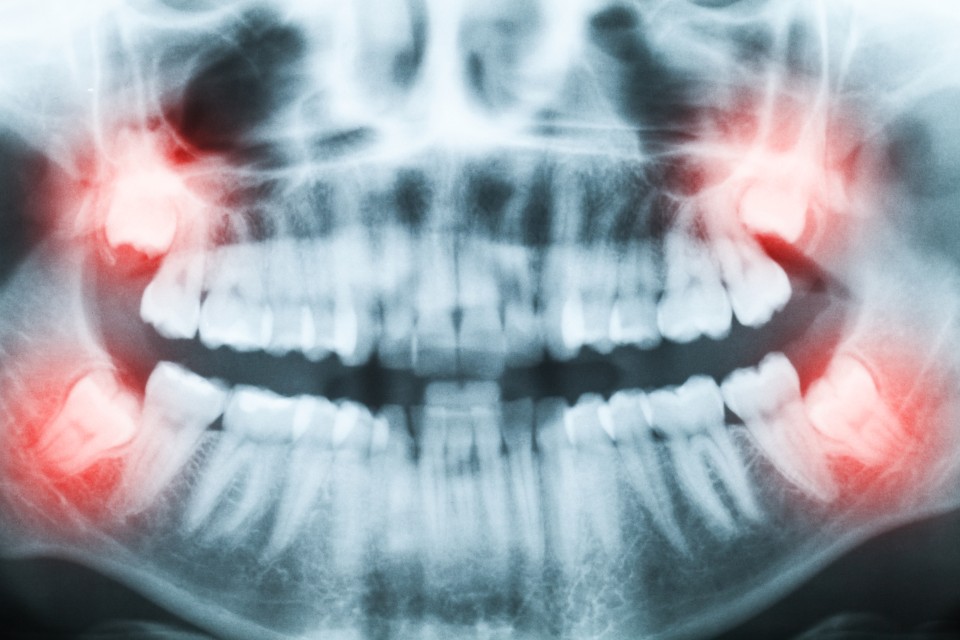

Wisdom teeth can emerge anytime in the late teenage years, 20’s or even in a person’s early 30’s. Dentists often recommend wisdom teeth be removed (wisdom teeth removal) before they begin to emerge, because their positioning can cause disruption or damage to surrounding teeth.

Before modern dentistry, it was helpful to have wisdom teeth emerge in late childhood/early adulthood. People simply lost teeth more often, and these third molars helped them go about eating and chewing properly. Nowadays, however, not many people have the extra room for wisdom teeth, and they tend to cause problems by becoming impacted—that is, emerge in a direction that crowds other teeth. Ultimately this pressure can disrupt the alignment of the rest of the teeth.

Beginning around age 12, routine digital X-rays can alert your doctor to potential problems… Before wisdom teeth start getting disruptive! We can then monitor the problem to determine if those mighty molars must go. If you still have your wisdom teeth as an adult, then take extra care to brush and floss properly. Wisdom teeth are the hardest to reach, so they are especially prone to decay and infection.